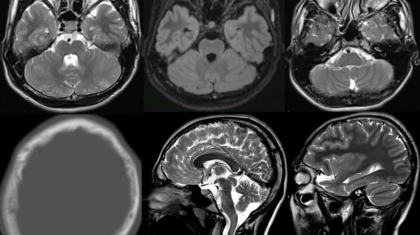

17-year-old female presenting with

Acute onset of right upper and lower limb weakness

Giddiness, Deviation of mouth and slurring of speech

Clinical Diagnosis:

Young stroke (6 hours 40 minutes from onset to imaging)